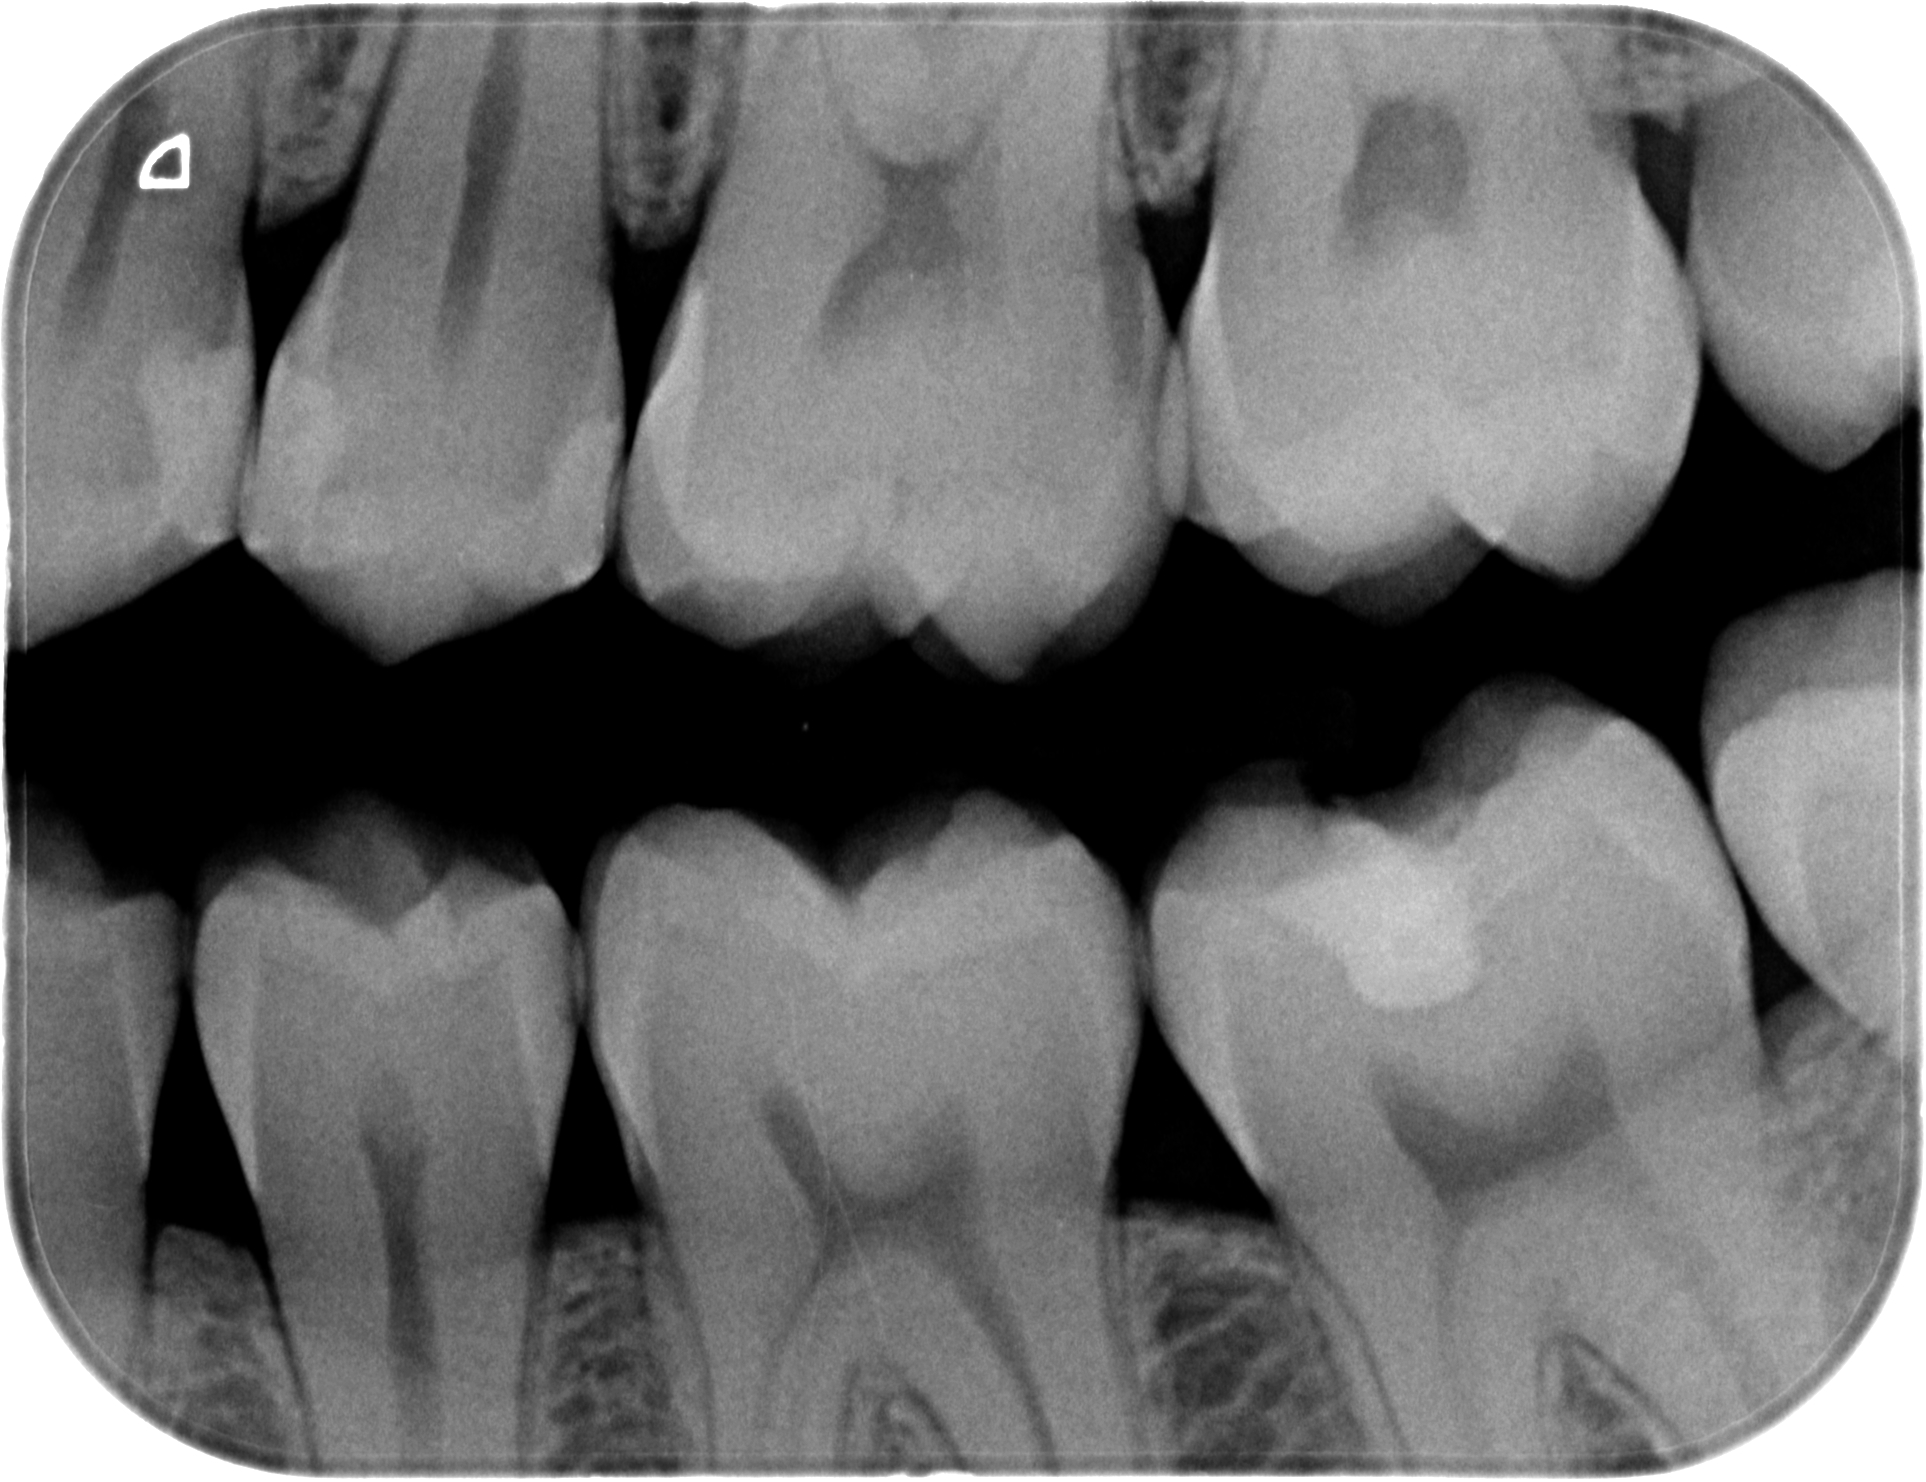

Dental X-ray showing molars and premolars with one tooth having a visible filling

Post-op bite wing radiograph, essential for verifying the adequacy of composite compaction.